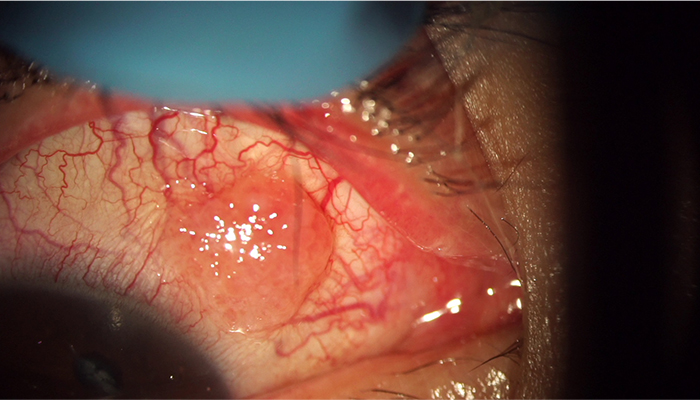

数年前に他院で重瞼術を行っています(埋没法)。

数日前から目がゴロゴロするので眼科へ行ったが、糸が取れなかったため紹介され当院を受診しました。

埋没法で使用したナイロン糸がまぶたの裏に露出し、角膜にキズを作っています。

それだけではなくそのキズに細菌が入り、角膜潰瘍となっているので、角膜の一部が白濁しています。

染色すると、角膜潰瘍の部分の上皮が無くなっているため、染色されている。

角膜にキズがあり、感染まで起こしているのでまぶたが腫れて、目が開かない眼瞼下垂の状態になってしまっています。

まぶたが思うように開かないため、眉毛が上がってしまっています。

まぶたの中の糸を除去すると、症状はすぐに改善します。

この症例では同時に皮膚の切除と筋肉の短縮も行ったところ、術後まだ1週間の時点ですが、重瞼がはっきりした綺麗な目にすることが出来ました。

糸が眼球を常に引っ掻いている状態で、キズが膨れて充血もしています。

このような場合には、糸の除去を行うしかありません。手術で糸を除去するとすぐに症状が改善します。手術1週間後には充血も取れて、綺麗な状態になりつつあります。